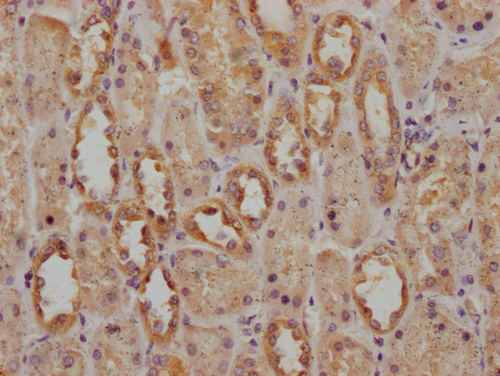

IHC image of CSB-PA754361LA01HU diluted at 1:200 and staining in paraffin-embedded human kidney tissue performed on a Leica BondTM system. After dewaxing and hydration, antigen retrieval was mediated by high pressure in a citrate buffer (pH 6.0). Section was blocked with 10% normal goat serum 30min at RT. Then primary antibody (1% BSA) was incubated at 4°C overnight. The primary is detected by a Goat anti-rabbit IgG labeled by HRP and visualized using 0.05% DAB.